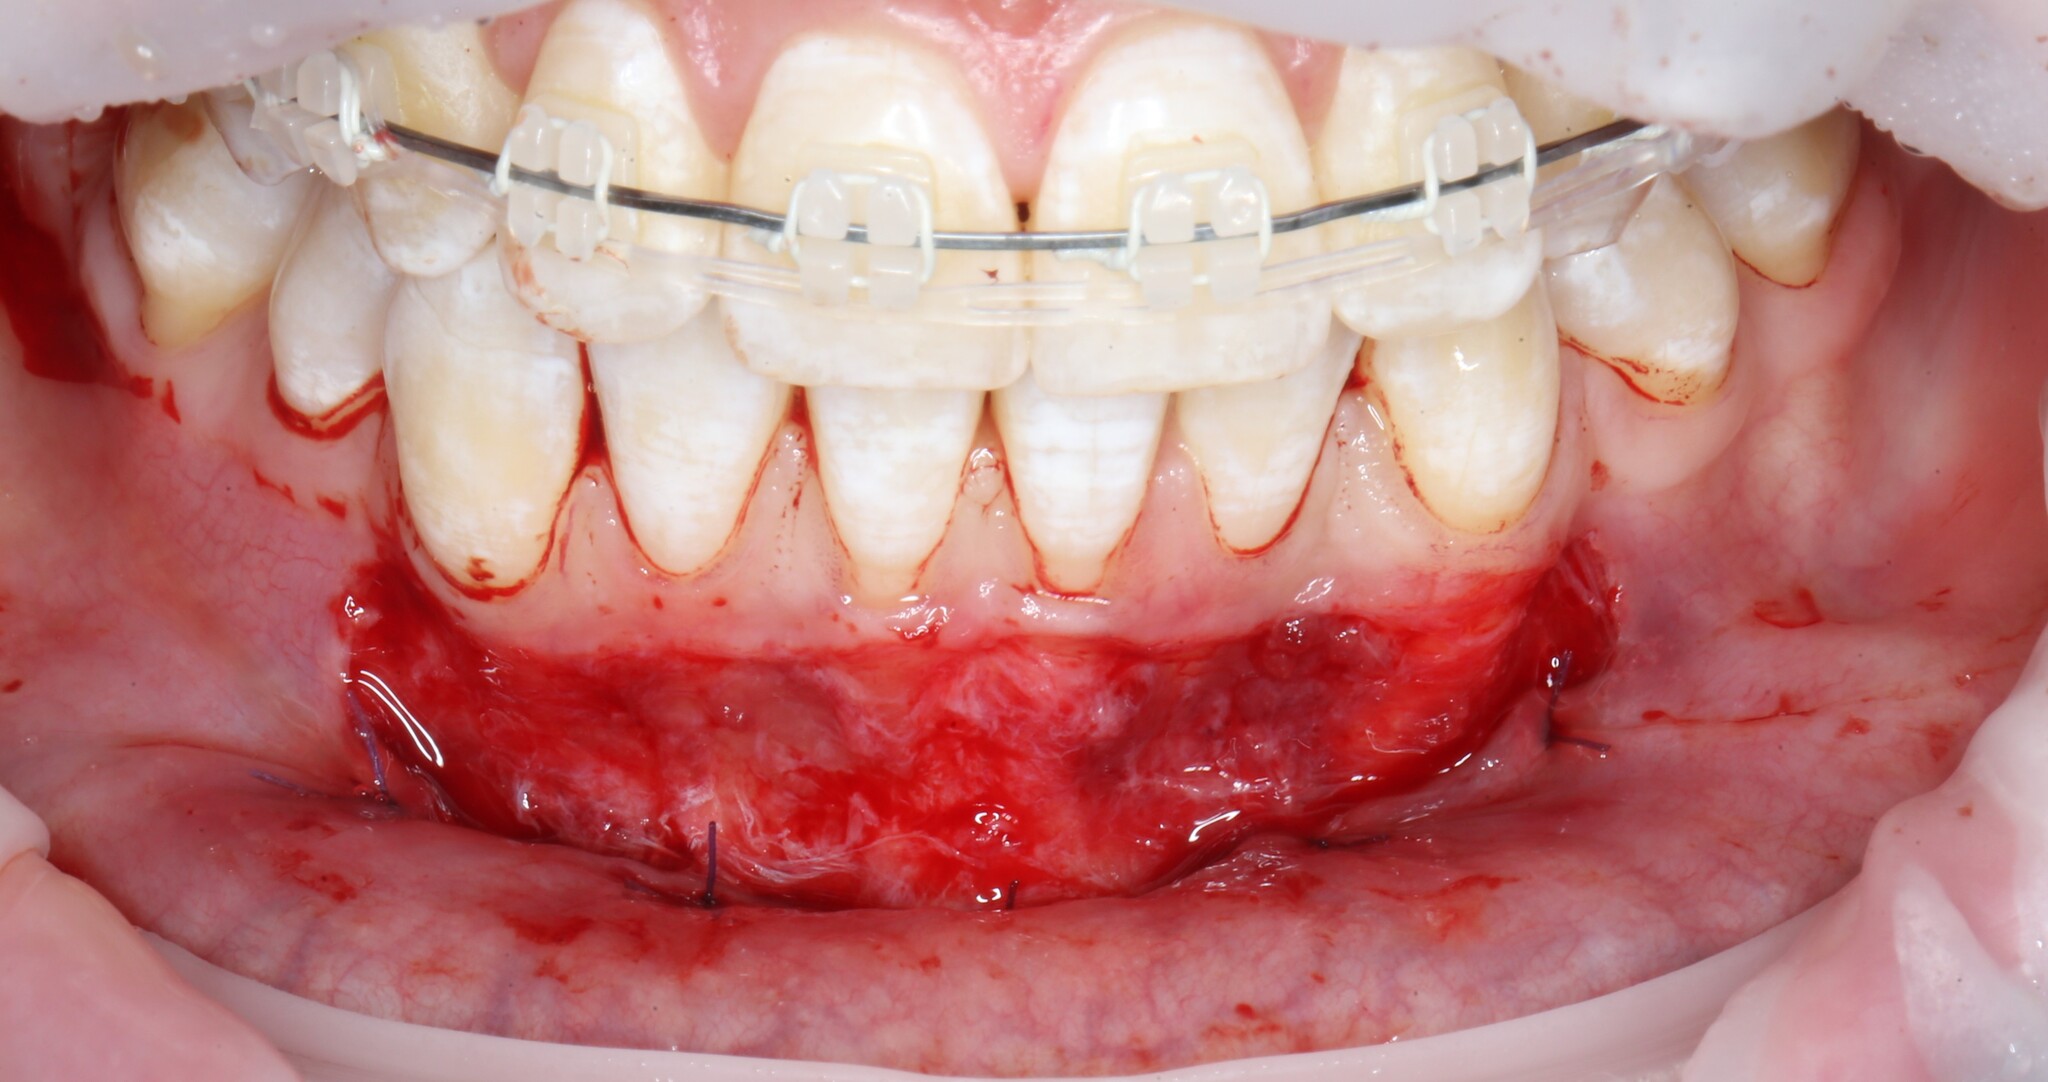

Получив аппетитную картинку для «Ганнибала», необходимо подшить ту часть, которую мы сместили вниз к надкостнице:

Такие швы необходимо наложить в нескольких местах для фиксации слизистой:

Для того, чтобы операция была менее травматична и не пришлось брать свою собственную слизистую, вырезав кусок с неба, используется коллагеновая мембрана. Выглядит она так:

Приложили:

Теперь подшиваем c одной стороны:

И с другой:

Операция закончена – ничего сложного нет: